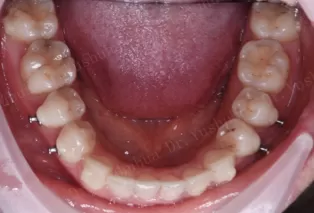

Intraoral photos